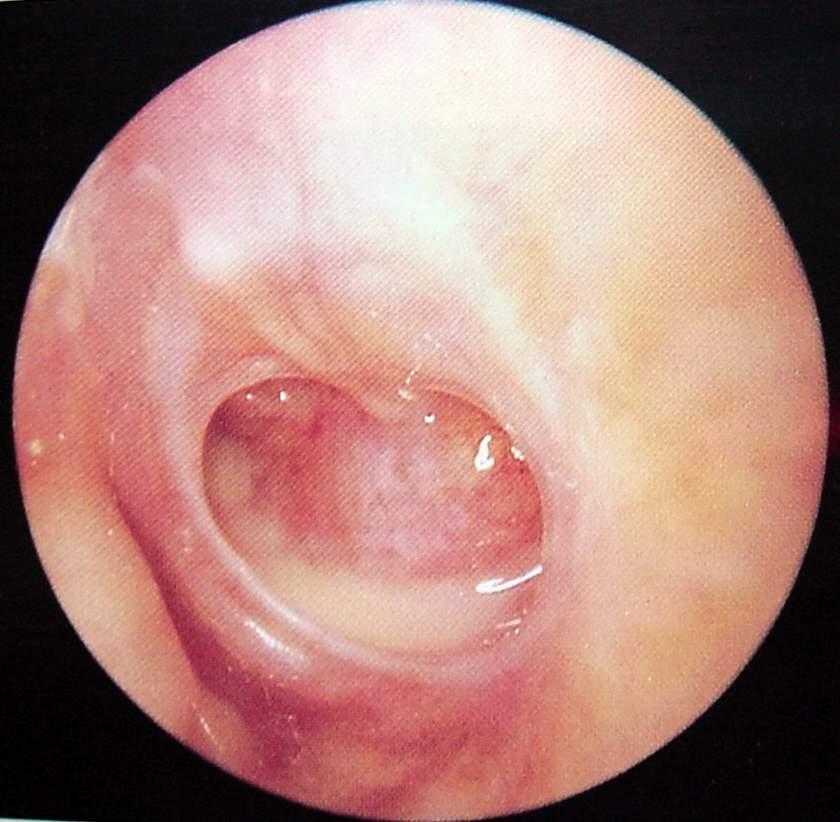

Ear Clinical Photos for Static Stations